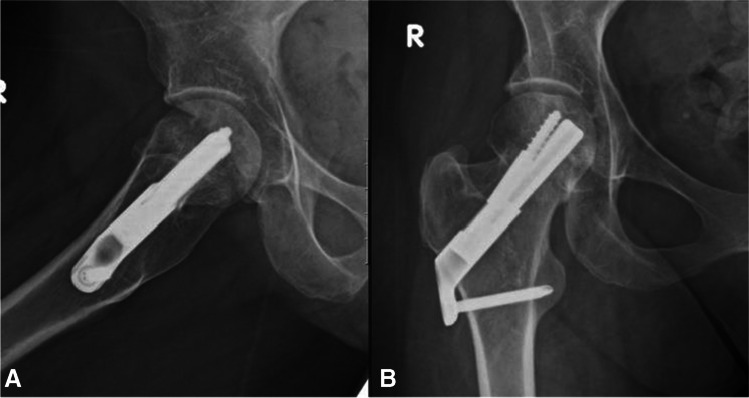

Fig. 1.

A, B AP and lateral radiographs showing intracapsular femur fracture of a 77-year-old female, which was admitted after a fall from standing height. Patient walks with no aids before the injury; her medical history consist of hypertension and dyslipidaemia

Fig. 2.

A, B AP and lateral radiographs postoperative day 1, demonstrating fixation of the fracture with FNS